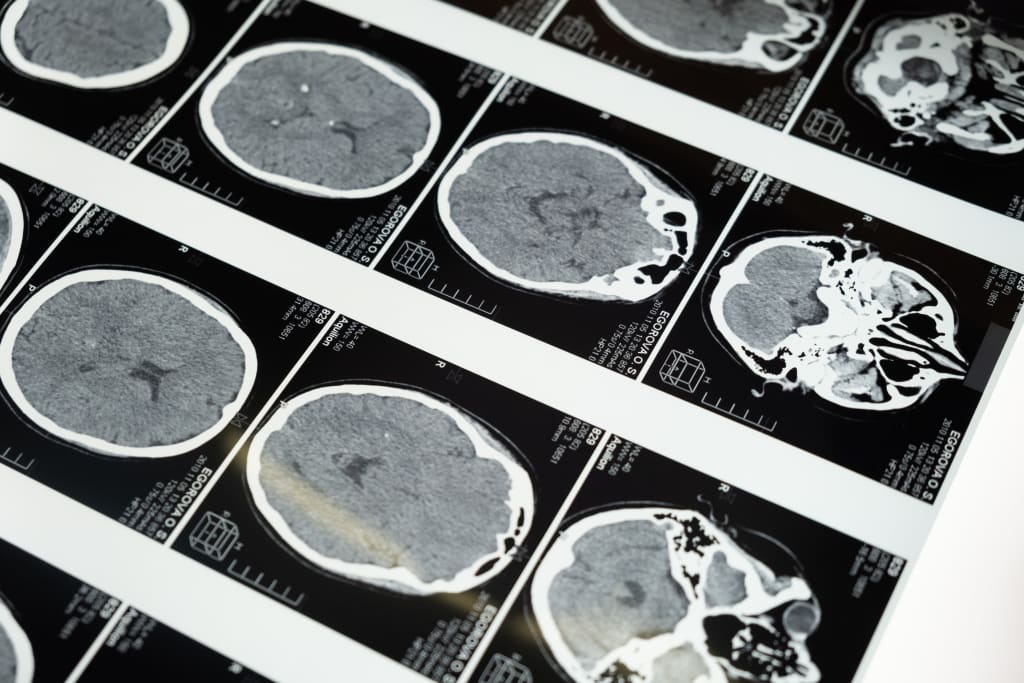

The human brain is the most complex organ in the body, and it is responsible for controlling all of our thoughts, movements, and behaviors. It is made up of billions of cells called neurons, which communicate with each other through electrical and chemical signals. The brain is divided into several regions, each of which performs specific functions.

One of the most well-known regions of the brain is the cerebral cortex, which is responsible for higher cognitive functions such as decision-making, problem-solving, and language processing. The cerebral cortex is divided into four lobes: the frontal lobe, which controls movement and helps us plan and make decisions; the parietal lobe, which is involved in sensation and perception; the temporal lobe, which is involved in hearing and memory; and the occipital lobe, which is responsible for vision.

Within the cerebral cortex, there are also several distinct areas that are responsible for specific functions. For example, the prefrontal cortex is involved in decision-making and social behavior, while the primary motor cortex is responsible for controlling voluntary movement. The primary somatosensory cortex processes touch, temperature, and pain sensations, and the primary visual cortex processes visual information.

Another important region of the brain is the hippocampus, which is involved in memory and spatial navigation. The amygdala, which is located in the temporal lobe, is involved in emotions and the fight-or-flight response. The basal ganglia, which are a group of nuclei located deep within the brain, are involved in the control of movement.

The brain is also home to the brainstem, which controls essential functions such as heart rate, breathing, and blood pressure. The brainstem is divided into three parts: the medulla oblongata, the pons, and the midbrain. The medulla oblongata is involved in controlling vital functions such as breathing and heart rate, while the pons is involved in the control of sleep and arousal. The midbrain is involved in the control of movement and the processing of sensory information.